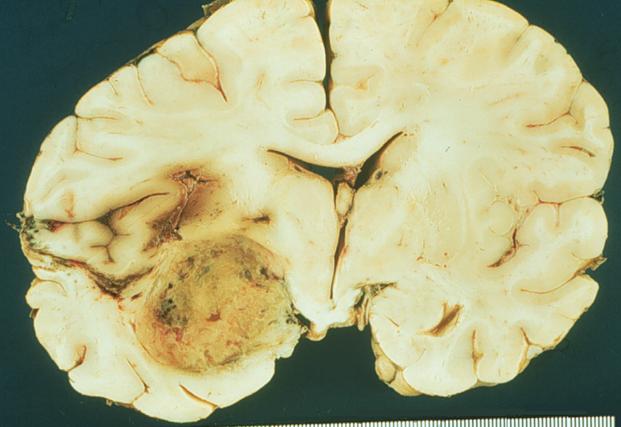

What is the most likely diagnosis for this brain lesion?

A) arteriovenous malformation

B) glioblastoma multiforme

C) infarction

D) pilocytic astrocytoma

E) radiation necrosis